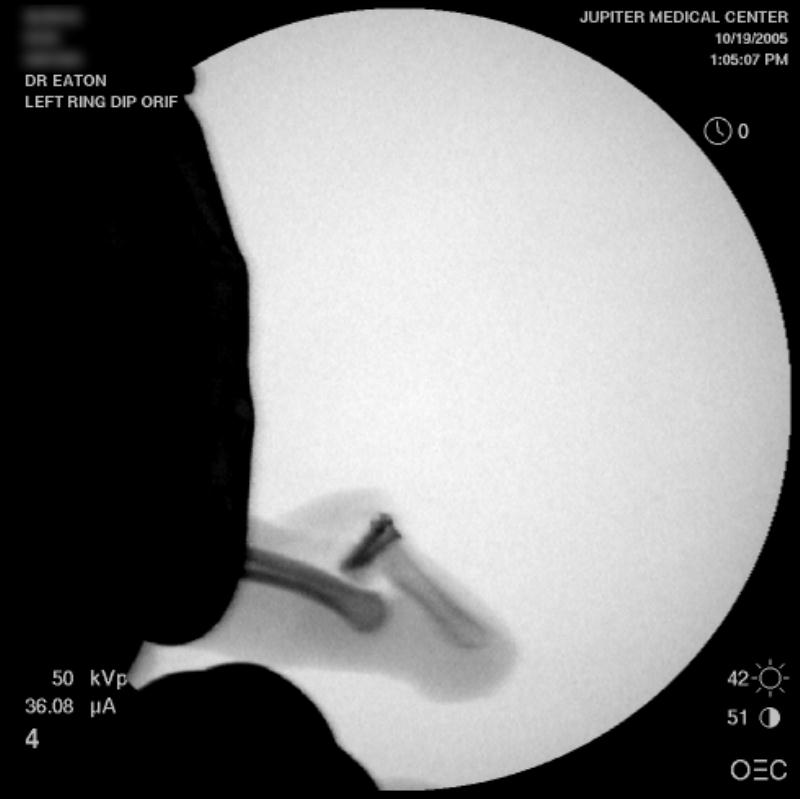

Intraoperative fluoros: The injury, reconstruction through a bayonette exposure, stable reduction.